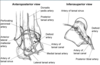

Describe the Arteries Providing Blood Supply to the Talus (6)

- Artery of the Tarsal Canal

- From Posterior Tibial A.

- Supplies Body

- Deltoid Artery

- From Artery of the Tarsal Canal

- Supplies Medial Body

- Direct Posterior Artery

- From Peroneal Artery

- Supplies Posteiro Process/Body

- Direct Superomedial Artery

- From Dorsalis Pedis

- Supplies Head & Neck

- Artery of the Tarsal Sinus

- From the Dorsalis Pedis & Peroneal A

- Supplies Neck & Lateral Body

- Perforating Peroneal A.

- From Peroneal A.

- Supplies Head & Neck

In general:

- Dorsalis Pedis A. - Supplies Head & Neck

- Peroneal A. - Supplies Head & Lateral Body

- Posterior Tibial A. - Supplies Tarsal Canal A. & Medial Body

- The main blood supply to the talus